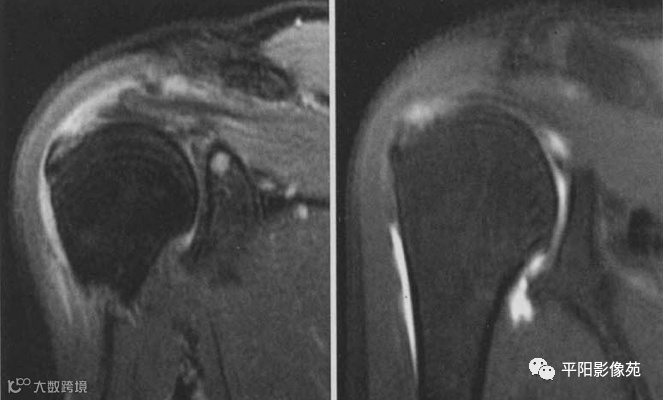

肌腱全层撕裂,示例

1、冈上肌肌腱全层撕裂,肌腱断端回缩

2、冈上肌肌腱全层撕裂,肌腱断端回缩,肩峰下-三角肌下滑囊积液

全层撕裂主要表现有:

肌腱连续性中断,裂隙由滑囊面贯穿至关节面,信号强度近似水信号强度,伴有肌腱回缩。